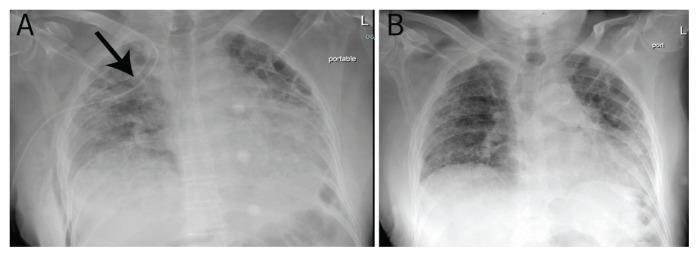

Severe acute respiratory syndrome coronavirus 2 (SARS-CoV-2), a novel coronavirus, represents an unprecedented global threat. We report a 78-year-old male patient who presented to the Emergency Department at a tertiary care hospital in Muscat, Oman, in June 2020 with a one-day history of right chest pain and severe breathlessness. The patient was an ex-smoker and known to have idiopathic pulmonary fibrosis (IPF) with two previous pneumothoraces in the left lung. On presentation, the patient was breathless with an oxygen saturation of 90% on room air. Chest X-ray demonstrated bilateral lung infiltrates and right-sided pneumothorax. The patient tested positive for SARS CoV 2. A chest drain was placed which resulted in good resolution of the pneumothorax. The patient's condition improved remarkably and he was discharged after 17 days of hospitalisation. To the best of the authors' knowledge, this was the first case of pneumothorax reported in a patient infected with COVID-19 who was known to have underlying IPF.

严重急性呼吸综合征冠状病毒 2(SARS-CoV-2),一种新型冠状病毒,代表了前所未有的全球威胁。我们报告了一名 78 岁的男性患者,他于 2020 年 6 月在阿曼马斯喀特的一家三级保健医院的急诊科就诊,病史为一天右侧胸痛和严重呼吸困难。患者曾是一名戒烟者,患有特发性肺纤维化(IPF),左肺曾有两次气胸。就诊时,患者呼吸困难,血氧饱和度在室内空气下为 90%。胸部 X 线片显示双肺浸润和右侧气胸。患者 SARS-CoV-2 检测呈阳性。放置了胸腔引流管,气胸得到了很好的解决。患者的病情显著改善,住院 17 天后出院。据作者所知,这是首例在已知患有特发性肺纤维化的 COVID-19 感染患者中报告的气胸病例。